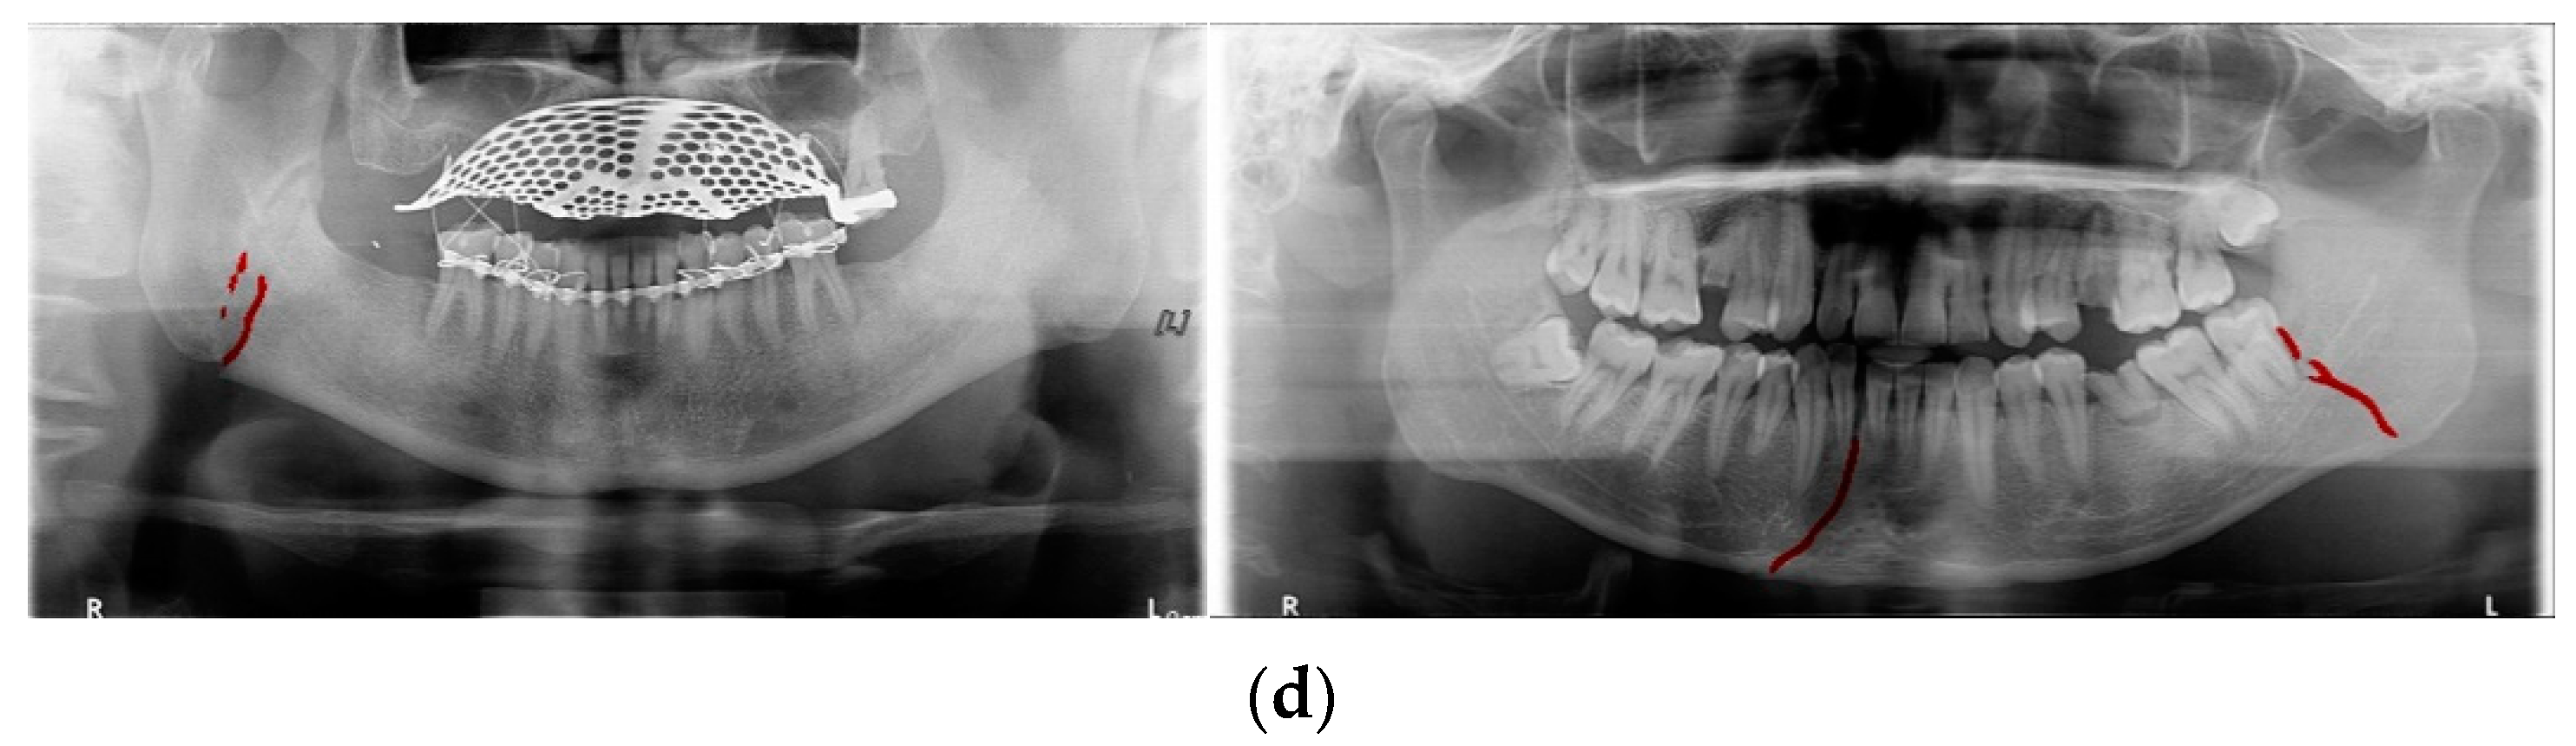

In Table 6, the parameters used for training are indicated, and in Figure 11, Figure 12 and Figure 13, the results of the doctor’s diagnosis, Mask R-CNN, YOLOv4, U-Net, LAT YOLOv4, and U-Net withYOLOv4 are compared. Figure 11 illustrates fractures in the angle and condylar regions, and in Mask R-CNN, the symphysis is misdiagnosed as a fracture. In Figure 12, the Mask R-CNN misdiagnoses the symphysis as a fracture, the result of the fact that the YOLOv4 module has better performance detecting angle fractures rather than does the LAT YOLOv4, as shown in Figure 12c,e. In short, the LAT-processed image does not always have the advantage of better revealing fractures compared with the normal panoramic radiograph.

Figure 12.

The comparison of mandibular fracture detection: (a) oral and maxillofacial radiologist, (b) Mask R-CNN (with colored polygons and boxes), (c) YOLOv4 (with a red box), (d) U-Net (with a red line), (e) LAT YOLOv4, and (f) U-Net with LAT YOLOv4 (with a red line).

For the case of Figure 12 images, it is possible to check the amount of local contrast improvement from the line profile information. In order to compare the changes in pixel brightness near angle fracture in the normal, SLAT and MLAT panoramic radiographs, the result of line profiles are shown in Figure 14 and Table 7. When comparing the maximum pixel brightness, minimum pixel brightness, average pixel brightness, and standard deviation in the line profile of the straight arrow near the angle fracture site, the normal panoramic radiograph has the largest standard deviation value of 5.6. Due to the characteristics of LAT processing, a dark area increases contrast, but as it becomes a bright area, contrast is maintained or slightly lowered.